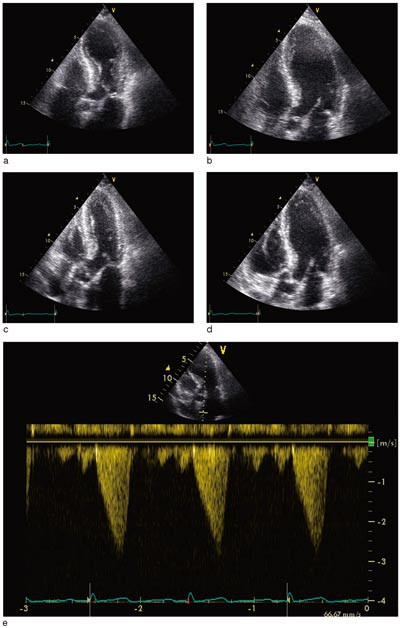

Pasient 3. 76 år gammel kvinne, som gjennom mange år hadde fått substitusjonsbehandling for hypotyreose. Ellers hadde hun stort sett vært frisk. Etter å ha deltatt i seniordans følte hun seg sliten og fikk ikke sove på grunn av smerter i venstre skulder. Morgenen etter hadde hun fortsatt smerter i skulderen og også i venstre side av thorax. Vel et halvt døgn etter smertedebut ble hun innlagt i sykehus. Hun var ved innleggelsen smertefri, og det var ingen kardiopulmonale svikttegn. Arterielt blodtrykk var 120/85 mm Hg, pulsfrekvensen 64 per minutt. Temperaturen ble målt til 38,1 °C. Ved auskultasjon fant man en systolisk bilyd grad III over prekordiet, ellers var det ingen vesentlige funn ved organstatus. EKG ved innkomst viste sinusrytme og lett ST-elevasjon i avledningene I, II og V₂ – V₆. Dagen etter innkomst var det noe mer tydelig ST-elevasjon i II, III og AVF, men i V₂ – V6 så man dype, negative og symmetriske T-takker uten ST-elevasjon. Det tilkom ingen Q-takker. Senere var det fullstendig normalisering av EKG (fig 2). Ekkokardiografi innkomstdagen viste akinesi av apex cordis og apikale tredel av venstre ventrikkel (fig 3a, 3b). Det var tydelig systolisk anterior bevegelse («SAM») av fremre mitralklaff, med betydelig trykkgradient i venstre ventrikkels utløpstrakt, målt til 45 mm Hg med doppler (fig 3e). Det var lettgradig mitralklaffinsuffisiens. Kontrollundersøkelse neste dag viste ingen vesentlig endring, men kontrollekkokardiografi fem dager etter innkomst viste tilnærmet full normalisering av venstre ventrikkels kontraktilitet (fig 3c, 3d). Trykkgradienten i venstre ventrikkels utløpstrakt var redusert til 20 mm Hg.

Hos mange av pasientene med transitorisk apikal ballonering av venstre ventrikkel er det observert obstruksjon i ventrikkelens utløpstrakt (2, 13), noe vi også observerte hos en av våre pasienter (fig 3). Det antas at noen pasienter ut fra hjertets anatomi og geometri er predisponert for obstruksjon i venstre ventrikkel, og at dette manifesteres ved kraftig adrenerg stimulasjon (13). Et prominerende basalt interventrikulærseptum, sammen med redusert venstre ventrikkel-volum, kan være årsaken til at kvinner er predisponert for obstruksjon i venstre ventrikkels utløpstrakt. Obstruksjon med trykkgradient i ventrikkelens utløpstrakt kan gi betydelig trykkøkning i apikale del av ventrikkelen, og dette kan være en del av forklaringen på hvorfor alltid apikale segmenter av venstre ventrikkel er akinetiske ved dette syndromet (7). Det finnes imidlertid flere andre forklaringer, blant annet at venstre ventrikkels apeks ikke har trelags myokardstruktur, og at apeks er grensesonen mellom perfusjonsområdene til de store koronararteriene (2).